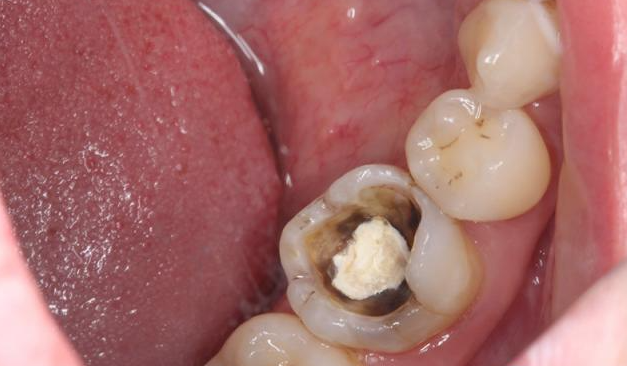

深龋近髓

深龋近髓要怎么处理呢?照书上预约去腐,安抚,垫底,充填